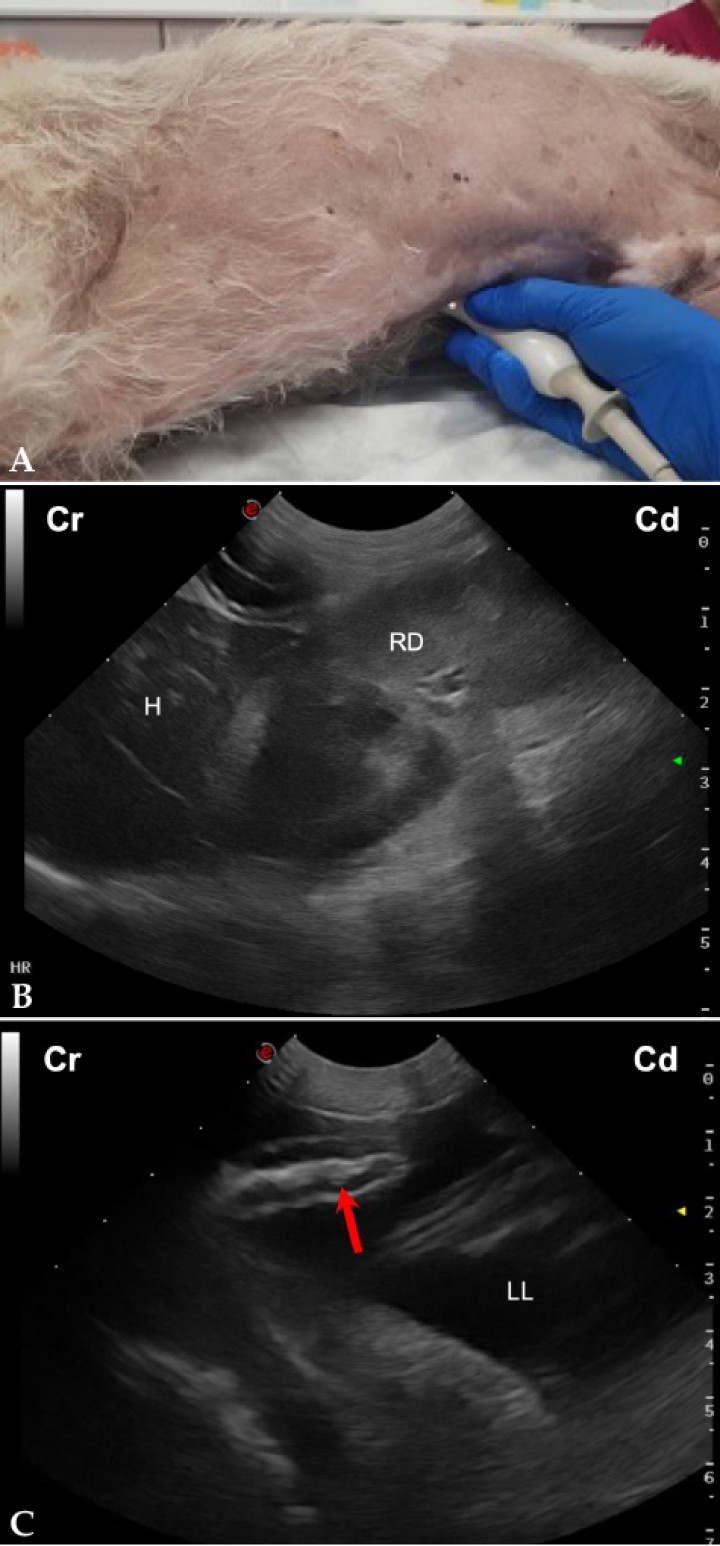

- Vista del flanco derecho (Fig. 4A): Permite la evaluación del área hepatorrenal (HR) y de la zona entre las asas intestinales, riñón derecho y pared abdominal (Figs. 4B y 4C).[ Boysen SR, Lisciandro GR: The Use of ultrasound for dogs and cats in the emergency room. AFAST and TFAST. Vet Clin Small Anim 2013; 43: 773-797. [PubMed] , Lisciandro GR: The abdominal FAST (AFAST) exam. En Lisciandro GR (ed): Focused ultrasound techniques for the small animal practitioner, Oxford, Wiley Blackwell, 2014; 17-43. , Kinns J: Abdomen. En Barr F, Gaschen L (ed): BSAVA Manual of canine and feline ultrasonography, Gloucester, BSAVA, 2011; 72-84. ]

<p>(<strong>A</strong>) Posicionamiento de la sonda de ecografía para obtener la vista del flanco derecho. (<strong>B</strong>) Imagen ecográfica del área hepatorrenal (HR) de un perro sano, en la que se observa el hígado (H) y el riñón derecho (RD) en corte longitudinal. Cr: craneal; Cd: caudal. (<strong>C</strong>) Imagen ecográfica de asas de intestino delgado obtenida de un perro con hemoabdomen durante la realización de la vista hepatorrenal, en la que se observa la presencia de moderada cantidad de líquido libre anecogénico (LL) entre las mismas, además de su corrugación (flecha roja). Cr: craneal; Cd: caudal.</p>

Figura 4

(A) Posicionamiento de la sonda de ecografía para obtener la vista del flanco derecho. (B) Imagen ecográfica del área hepatorrenal (HR) de un perro sano, en la que se observa el hígado (H) y el riñón derecho (RD) en corte longitudinal. Cr: craneal; Cd: caudal. (C) Imagen ecográfica de asas de intestino delgado obtenida de un perro con hemoabdomen durante la realización de la vista hepatorrenal, en la que se observa la presencia de moderada cantidad de líquido libre anecogénico (LL) entre las mismas, además de su corrugación (flecha roja). Cr: craneal; Cd: caudal.